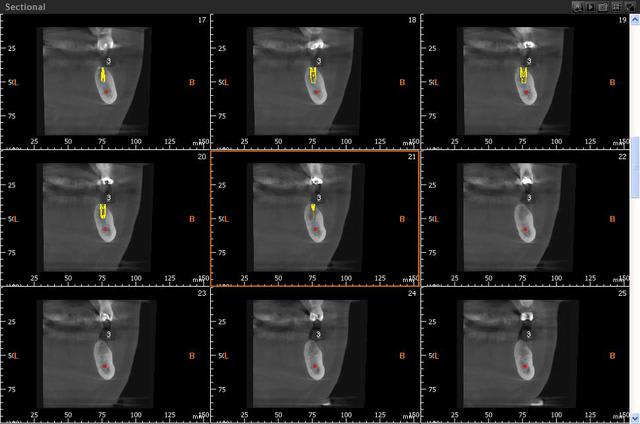

Sagital jxcd3g - Eugenol

Coupe wivo5x - Eugenol

3d gxwzhi - Eugenol

Image r6habu - Eugenol

Thomas Crown

16/10/2014 à 12h41

Humator, une image avec métal si tu peux, pour voir les artefacts et qualité de résolution.

Merci!

Humator t9r5wy - Eugenol

humator

16/10/2014 à 15h19

voilà un cas avec du metal:couronnes sur les dents bordant l'édentement, et en haut. c'est sur la reconstruction 3d que ça perturbe le plus. Cela dit, tu peux "couper" les artefacts pour les faire disparaitre, si tu souhaites une belle image en volume.

C'est vrai que certaines reconstitutions 3d sont plus moches, quand il y a beaucoup de métal, mais ça ne perturbe pas les coupes.

j'essaye de t'en trouver d'autre bien moches...

ici je n'ai pas "nettoyé" la reconstruction 3d

--

N.Hum